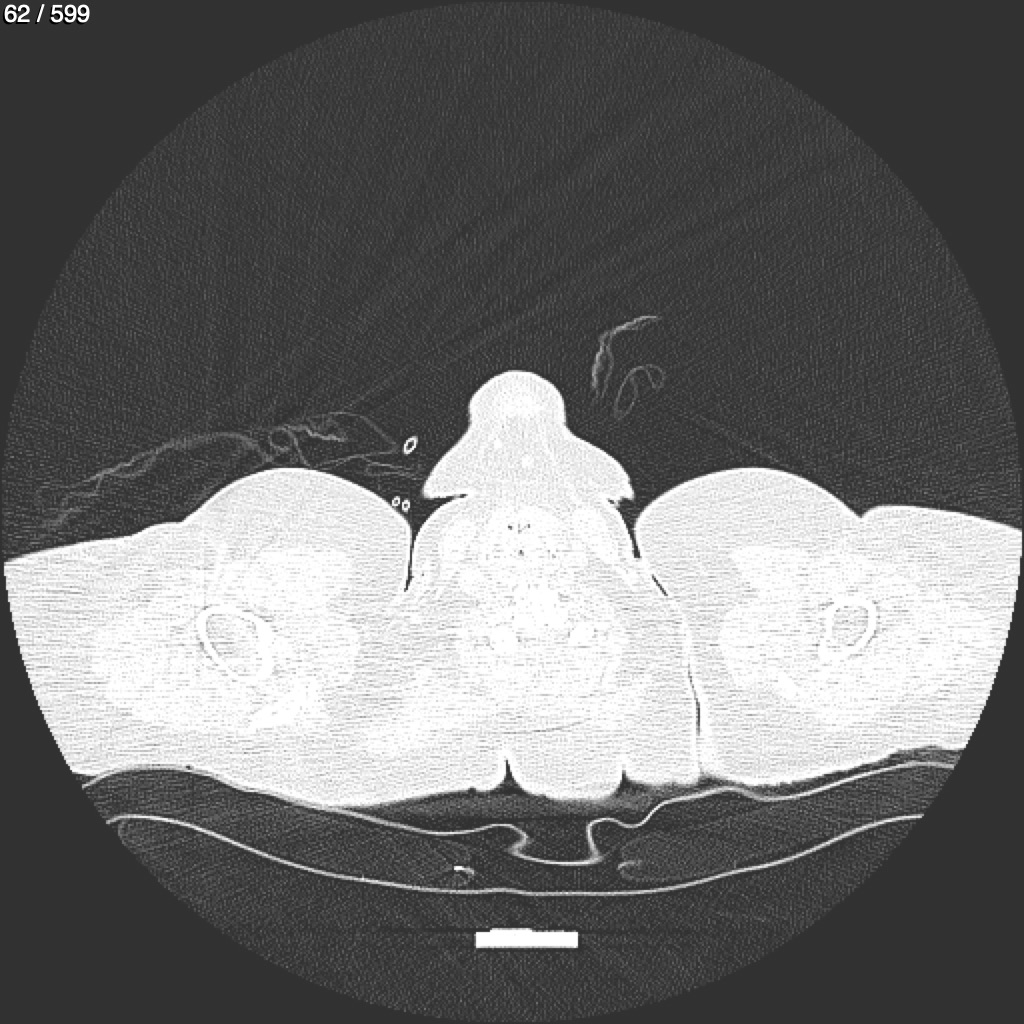

Home G​l​o​r​i​a​ ​G​l​a​d​y​s​ ​B​e​a​s​l​e​y​ ​-​ ​T​ó​r​a​x​ ​T​o​r​a​x​_​S​i​m​p​l​e​ ​(​A​d​u​l​t​o​)